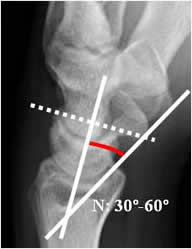

La inclinación volar:

Trazado en la Rx lateral. Angulo formado entre la perpendicular al eje del radio y una línea que une su extremo anterior y posterior. El valor normal es entre 0 y 22º (12). Cualquier valor negativo es patológico. (13). (Fig 49 y 50).

Fig 49. Inclinación volar.

Rx lateral de muñeca. Angulo formado entre la perpendicular al eje del radio y una línea que une la parte anterior y posterior del radio distal.